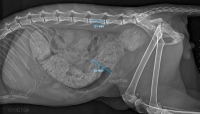

Megacolon is a consequence of long- standing constipation and is considered to be the end stage of large bowel dysfunction due to a permanent loss of colonic structure and function.Due to the fact that megacolon is associated with high morbidity and because conservative treatment gives only temporary relief, many owners elect euthanasia for their pet rather than chronic ineffective medical management with luxatives and enemas.The main goal of the surgery is to improve the quality of life of the patient by the surgical removal of the diseased large bowel.